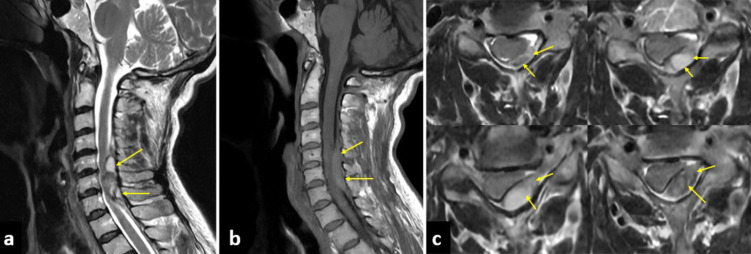

Case description: We report a 64-year-old woman with hypertension and a history of breast cancer who presented with chest and upper back pain, accompanied by left arm numbness. Mildly elevated troponin levels led to an initial diagnosis of acute coronary syndrome (ACS). Brain imaging was unremarkable, and coronary angiography revealed normal vessels. However, progressive left-sided hemiparesis and urinary retention prompted cervical magnetic resonance imaging, which revealed a subacute epidural hematoma at the C5-C7 level. Urgent decompressive hemilaminotomy was performed, resulting in gradual neurological recovery. By postoperative day 10, the patient had regained full motor strength.